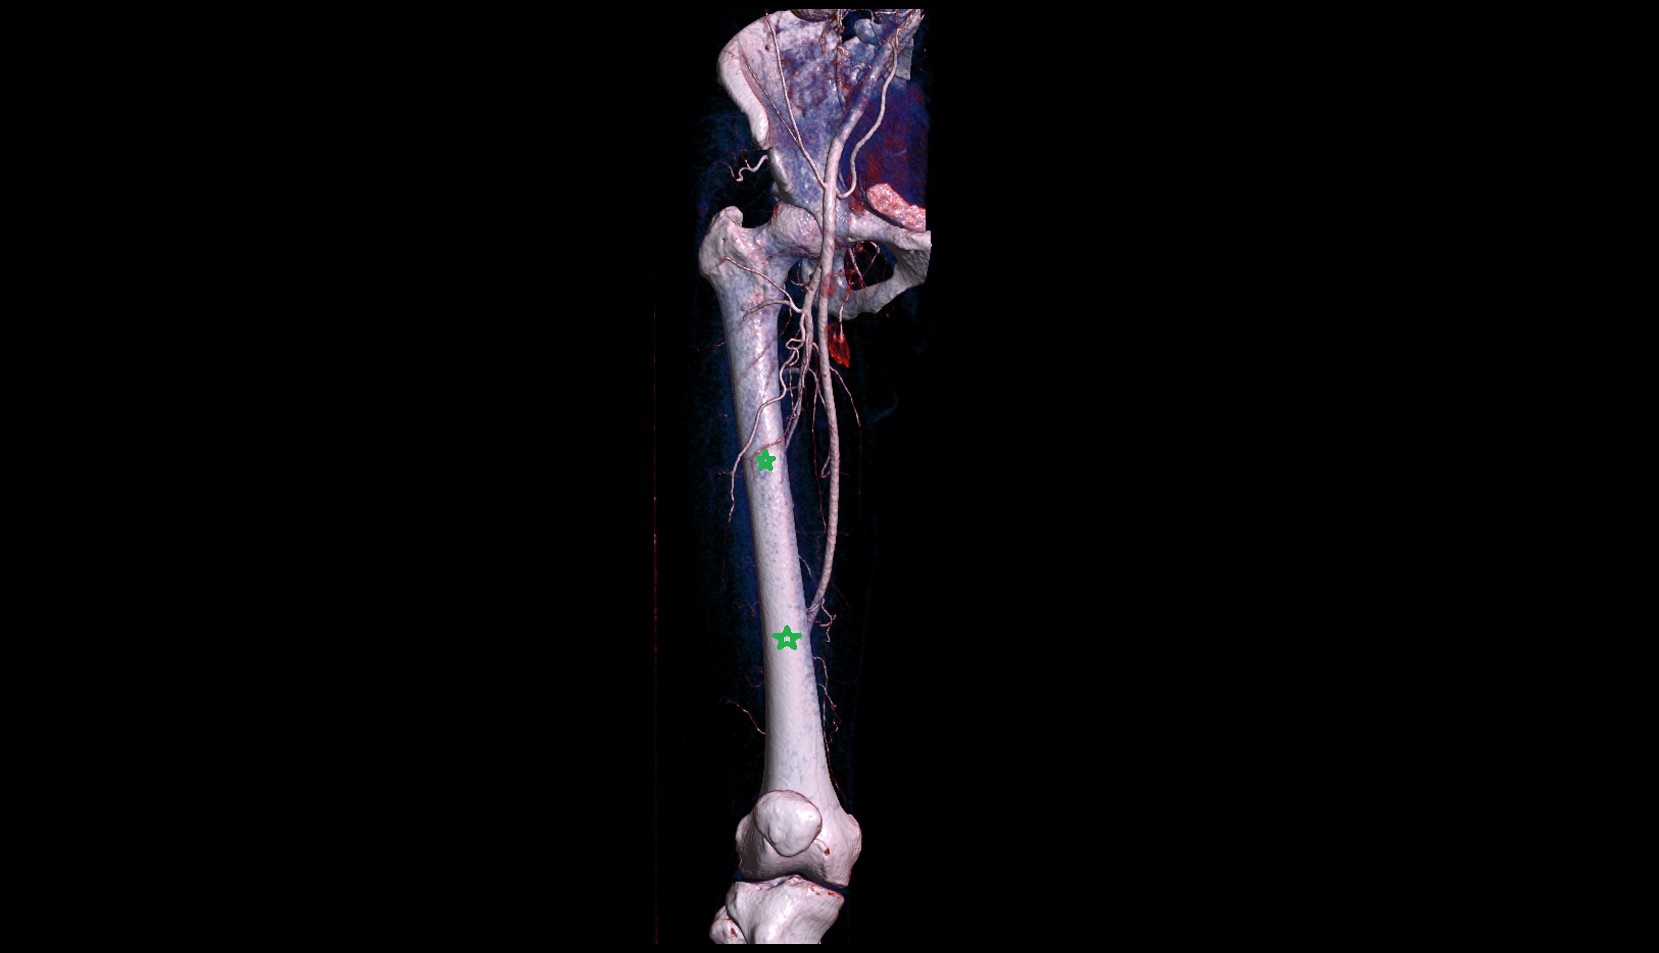

- Popliteal artery

- Posterior tibial artery

- Anterior tibial artery

- Fibular artery